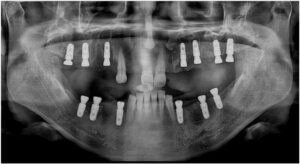

임플란트 식립을 진행하고

충분한 시간이 지났을 때

잇몸뼈와 임플란트가

단단히 결합된 것을 확인하고

최종 보철물 제작을 위한

과정을 진행하였는데요.

양측 어금니 보철물에 맞춰

위아래 앞니 브릿지 보철물도

같이 제작을 도와드렸으며,

최종 보철물은

자연치아와 강도가 유사하고

심미적인 지르코니아로

마무리해 드렸습니다.

모든 치료가 마무리된

구강 내 사진과

파노라마 사진인데요.